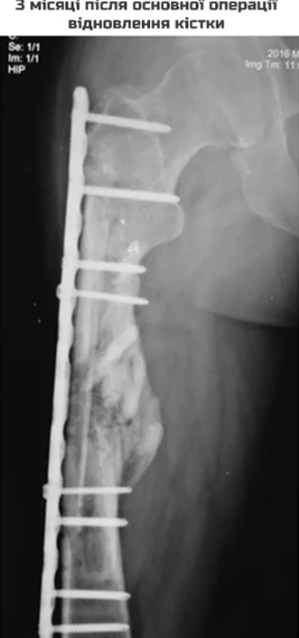

Запитання 23

НЕОПЕРОВАНИЙ ПЕРЕЛОМ ЦІЄЇ КІСТКИ І В ЦЬОМУ МІСЦІ ПРИЗВЕДЕ ДО СМЕРТІ В СЕРЕДНЬОМУ ЧЕРЕЗ КІЛЬКА РОКІВ. А ЦІ РОКИ ПЕРЕТВОРЯТЬСЯ НА СИДЯЧІ АБО ЛЕЖАЧІ МУКИ. ЯКОЇ КІСТКИ І ЯКОЇ ЇЇ ЧАСТИНИ?

варіанти відповідей

HUMERUS, ХІРУРГІЧНА ШИЙКА

ВЕРХНЬОГО ДІАФІЗА

FEMUR, ШИЙКА

ULNA, ШИЙКА

ПРОКСИМАЛЬНОГО ЕПІФІЗА

ДИСТАЛЬНОГО ЕПІФІЗА

HUMERUS, ШИЙКА

RADIUS, ШИЙКА